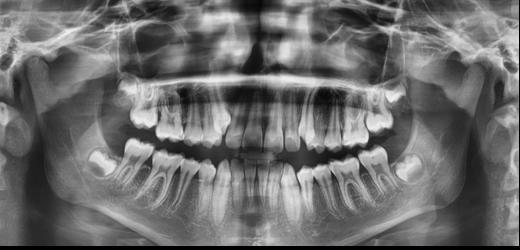

Figura 1. Radiografía inicial de la paciente. Se observa edentulismo total superior, a excepción del molar del primer cuadrante, indicado para exodoncia. En la mandíbula se aprecia pérdida ósea horizontal generalizada secundaria a la evolución de la enfermedad periodontal.

En la radiografía inicial (Figura 1) se observa la pieza 17 con pérdida ósea significativa, así como una reabsorción ósea homogénea a lo largo de todo el arco superior. En la arcada inferior se aprecia pérdida ósea horizontal generalizada y defectos localizados, como una lesión en cuña en la pieza 46. Ante esta situación, se decide realizar la exodoncia del molar remanente del

El mantenimiento periodontal y la implicación de la paciente en las medidas de autocuidado se mantuvieron de forma constante durante 23 años (Figura 25). La ortopantomografía realizada en una de las visitas de control mostró estabilidad completa de los implantes, sin signos radiográficos de pérdida ósea patológica.